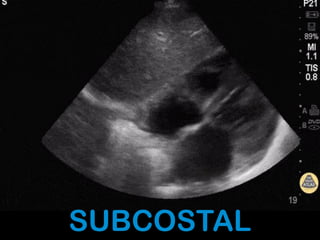

SUBCOSTAL